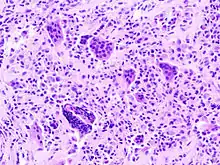

| Micrograph of diffuse TGCT, also known as pigmented villonodular synovitis. H&E stain. | |

Diffuse TGCT is sometimes referred to as pigmented villonodular synovitis (PVNS), conventional PVNS, and D-TGCT.[1]: 1 [4]: 361 [6]: 1 [2]: 102

Diffuse TGCT occurs less frequently and is locally aggressive (in some cases, tumors may infiltrate surrounding soft tissue).[3]: 245 [1]: 1 [2]: 102 [6][6]: 1 It most commonly affects people under 40 years old, though the age of occurrence varies.[2]: 102 Diffuse TGCT may occur inside a joint (intra-articular) or outside of a joint (extra-articular). Intra-articular tumors typically occur in the knee (approximately 75% of cases) and hip (approximately 15% of cases).[2]: 102 Extra-articular tumors are usually found in the knee, thigh, and foot.[2]: 101 Symptoms include swelling, pain, sensitivity, and/or limited range of motion.[2]: 102 The rate of reoccurrence is estimated to be 18-46% for intra-articular tumors and 33-50% for extra-articular tumors.[2]: 103 [6]: 1